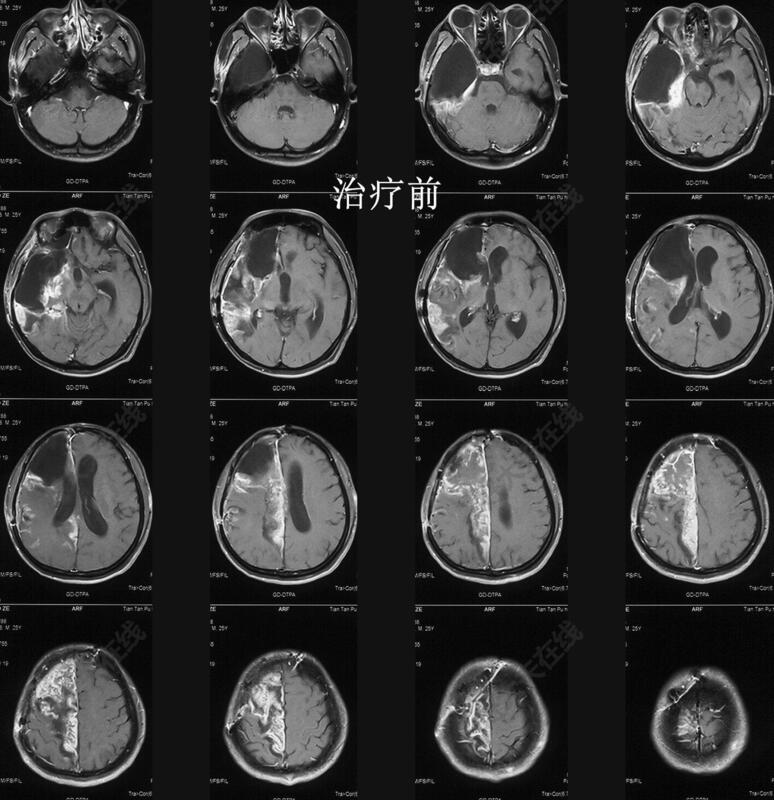

治疗前

胶质母细胞瘤放化疗后,外院复查示肿瘤复发。患者一般情况差,偏瘫,平车入室,严重营养不良(178cm,45kg)。口服替莫唑胺出现重度骨髓抑制。多个医生均建议放弃治疗。